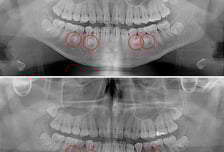

20대 김호영(가명) 씨는 어린 시절부터 치아가 고르지 못하고 자주 잇몸이 붓는 등 구강 건강이 좋지 않았다. 다들 그러려니 하며 대수롭지 않게 생각했지만, 몇 년 전 치과 X선 촬영에서 치아가 많은 '과잉치'를 진단받았다. 시간이 지나면서 치아 배열이 점점 더 불규칙해지고 지금은 음식을 씹는 것조차 어려움을 겪고 있다. 일반적으로 사람의 구강에는 28개의 영구치와 4개의 사랑니가 나와 총 32개의 치아가 자란다. 이보다 더 많거나, 불필요한 치아가 추가로 생기는 경우를 과잉치라 한다. 정확한 원인은 밝혀지지 않았지만 부모나 형제에게 과잉치가 있으면 발생 확률이 높아지는 것으로 보고된다. 대부분 턱뼈 내에 매복돼 있어 보호자는 물론 당사자조차 모르는 경우가 많다. 과잉치는 '구강 내 시한폭탄'으로 비유될 만큼 다양한 구강 문제를 일으킨다. 치아의 정상적인 맹출(치아가 잇몸 속에서부터 잇몸을 뚫고 올라오는) 과정을 방해하기 때문이다. 특히 영구치가 자리 잡는 6~15세 사이에는 더욱